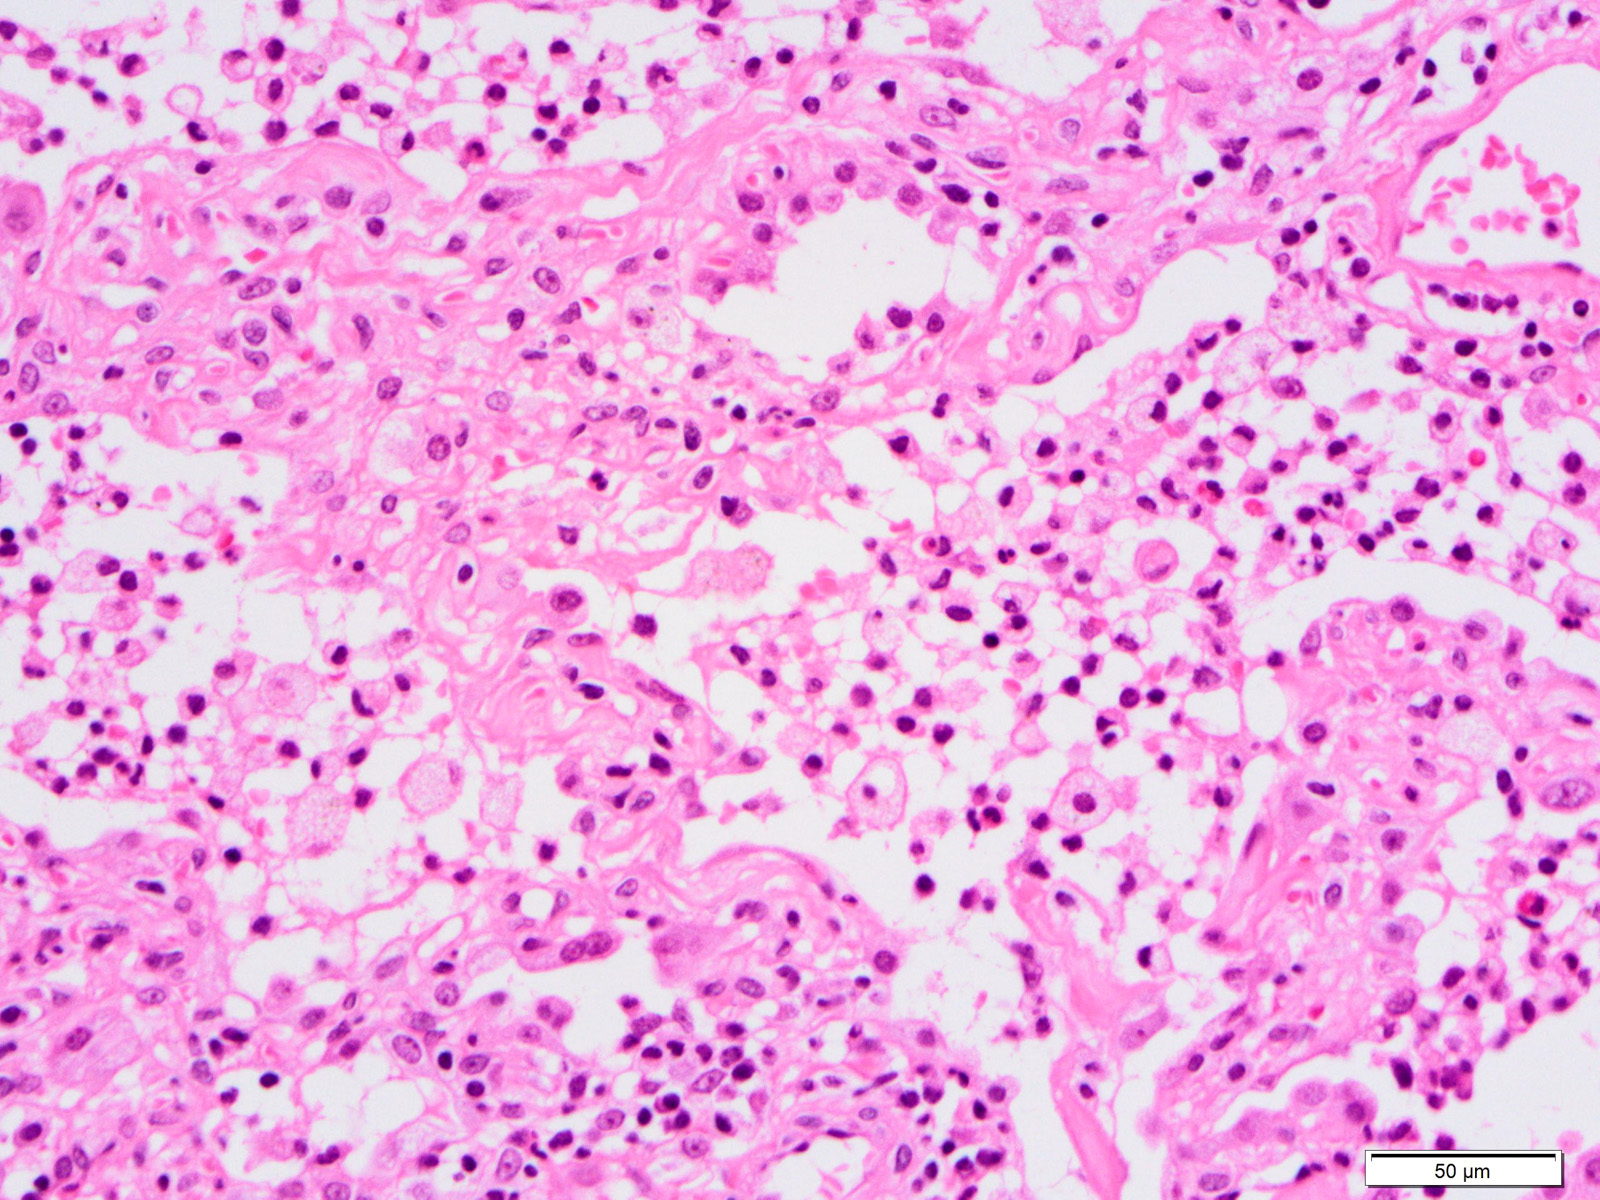

Microscopic (histologic) description

- Histopathology of DAD progresses from exudative (acute) phase through proliferative / organizing (subacute) phase to chronic fibrotic phase roughly corresponding to the period of ARDS (Am J Pathol 1976;85:209, Arch Pathol Lab Med 2010;134:719, Clin Chest Med 2000;21:435, N Engl J Med 2000;342:1334)

- Exudative (acute) phase

- Alveolar change

- Hyaline membranes on alveolar duct or sacs

- Interstitial and intra-alveolar edema

- Collapsed alveoli

- Epithelial change

- Denudation and necrosis of type I pneumocytes

- Vascular change

- Necrosis of endothelial cells

- Neutrophil aggregation

- Microthromboemboli

- Hemorrhage

- Alveolar change

Microscopic (histologic) images

Contributed by Akira Yoshikawa, M.D. and Yale Rosen, M.D.